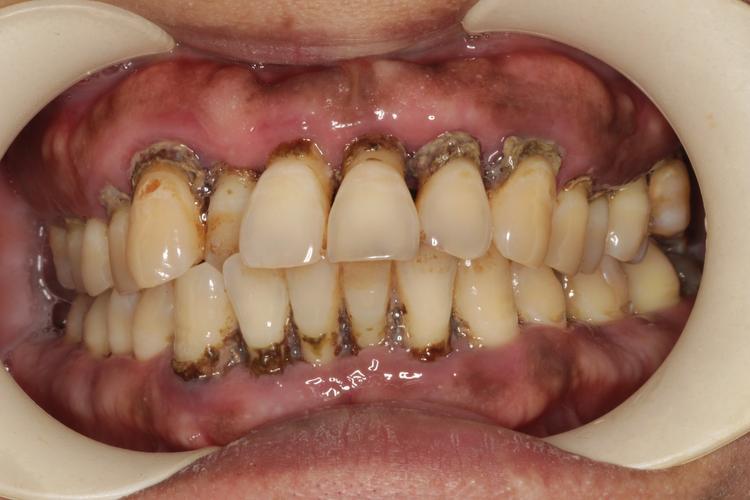

慢性牙周病是口腔领域常见的慢性炎症性疾病,主要由牙菌斑生物膜引发,累及牙龈、牙周膜、牙槽骨等牙周支持组织,临床表现为牙龈出血、牙周袋形成、牙槽骨吸收及牙齿松动甚至脱落,对于因慢性牙周病导致牙齿缺失的患者,种植牙是恢复咀嚼功能与美观的理想修复方式,但牙周病的存在会增加种植难度与风险,需系统治疗与严格管理。

慢性牙周病的核心病理改变是牙槽骨持续性吸收,正常情况下,牙槽骨为种植体提供稳定的骨结合基础,而牙周病患者的牙槽骨常出现水平吸收或垂直吸收,骨量不足、骨密度降低,可能导致种植体初期稳定性差、骨结合失败风险升高,牙周袋内存在的致病菌(如具核梭杆菌、牙龈卟啉单胞菌等)可能种植手术时种植体表面,引发术后感染,甚至导致种植体周围炎——这是种植牙远期失败的主要原因之一,研究显示,未控制的牙周病患者种植体周围炎发生率可达20%-30%,显著高于牙周健康者。